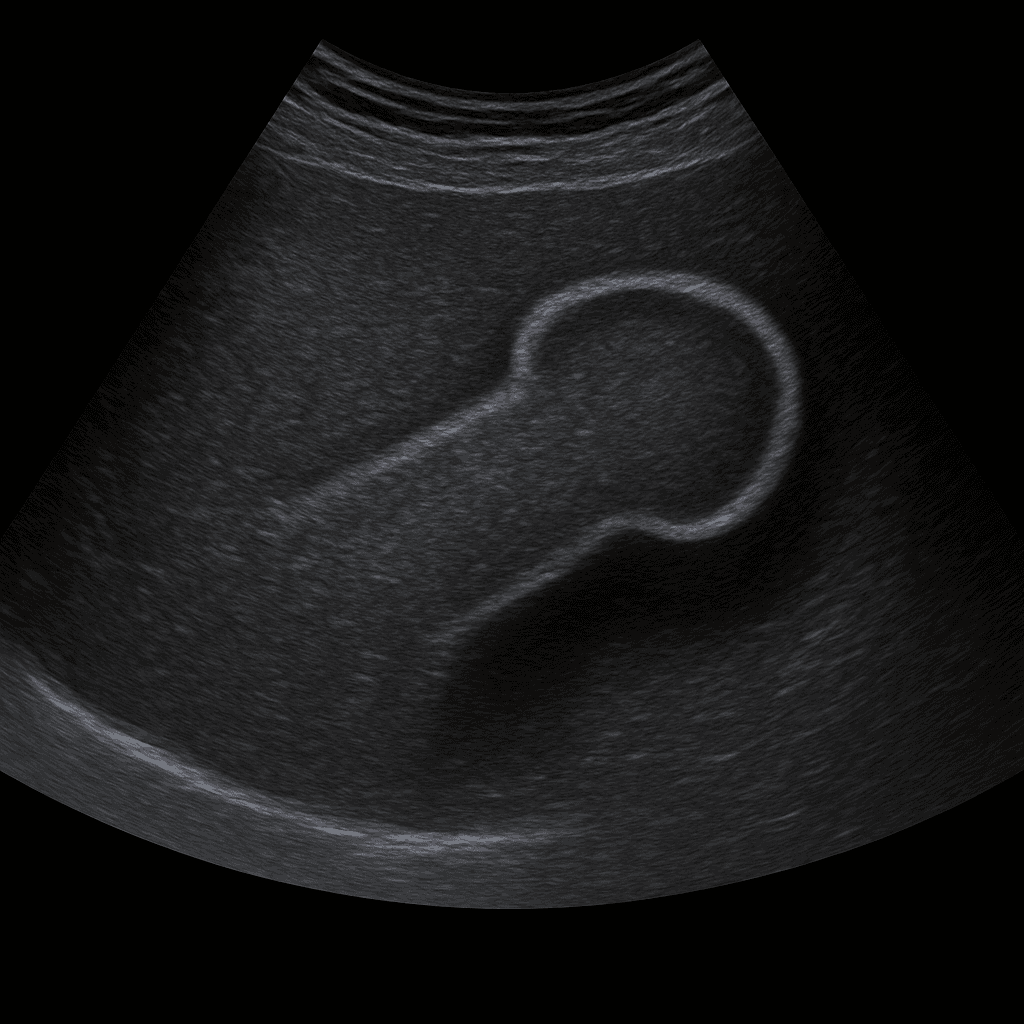

Ett ultraljud av penis används för att undersöka vävnad, blodflöde och eventuella strukturella förändringar i penisskaftet. Undersökningen utförs av specialistläkare inom radiologi och ger bilder i realtid som kan visa kärlförändringar, ärrbildning, förkalkningar eller tecken på skador. Ultraljud penis används ofta vid smärta, svullnad, kurvatur eller misstänkt kärlpåverkan.

Undersökningen rekommenderas vid besvär som smärta, svullnad, trauma eller när penisskaftet har förändrad form eller böjning. Den används även vid misstanke om Peyronies sjukdom (plackbildning eller ärr i svällkropparna) samt vid utredning av erektionsproblem kopplade till blodflödet.

Till skillnad från MR eller DT, som används vid mer omfattande vävnadsskador eller tumörutredning, är ultraljud en snabb, strålningsfri och effektiv metod för att bedöma kärlflöde och mjukdelar i penisskaftet. Med dopplerteknik kan läkaren analysera blodflödet i svällkropparna i realtid.

Undersökningen utförs vanligtvis när du ligger på rygg. En gel appliceras på huden och läkaren för ultraljudsproben längs penisskaftet för att bedöma vävnad och kärlflöde. Undersökningen tar cirka 10–15 minuter och är helt smärtfri. Vid behov används dopplerteknik för att studera blodcirkulationen i svällkropparna, ibland efter att ett kärlvidgande läkemedel har injicerats för att simulera erektion.